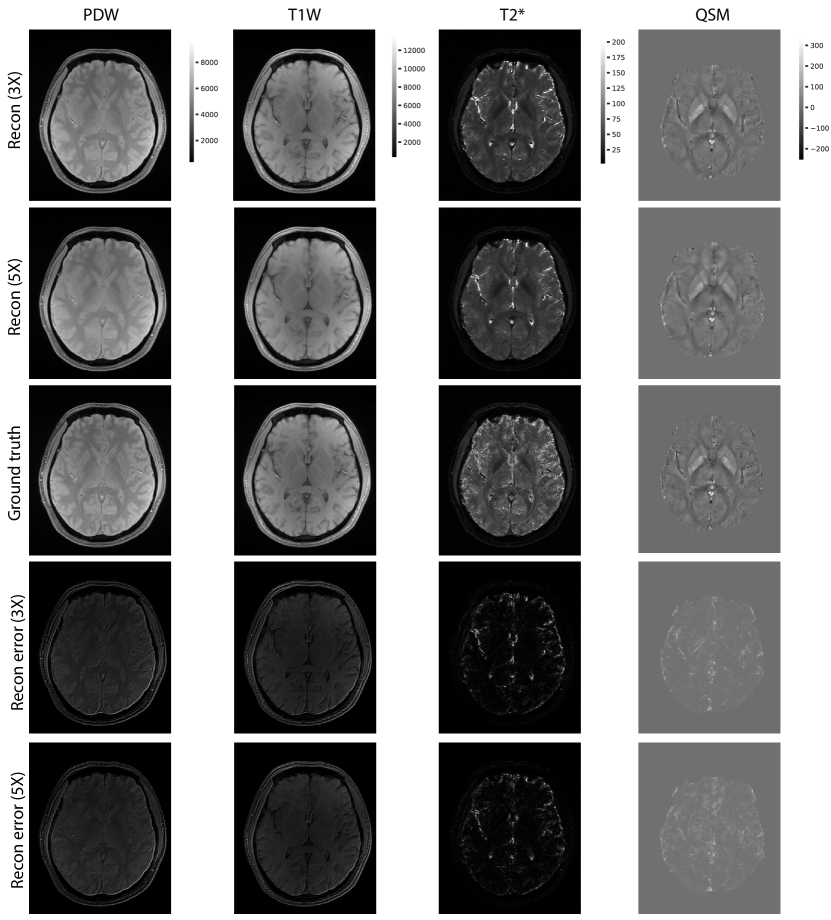

Figure 3: Examples of reconstructed PDW, T1W, T2* and QSM images at 3X and 5X accelerations. The parametric images were calculated based on all the reconstructed echo images in the scan. The same 2D axial slice from each 3D image is plotted.

Figure 2 shows the examples of reconstructed MULTIPLEX echo images from the test dataset. The reconstruction results at 3X acceleration are quite similar to the ground truth, while the results at 5X acceleration show relatively worse reconstruction quality. Compared to the ground truth, the DL reconstructions have less ringing artifacts and noise. Table 1 shows the quantitative results for the reconstructed echo images at 3X and 5X accelerations, which are consistent with the visual examples in Figure 2. Based on the reconstructed echo images, we also calculated the parametric images such as PDW, T1W, T2* and QSM (Figure 3 and Table 2), which are also similar to the ground truth results.